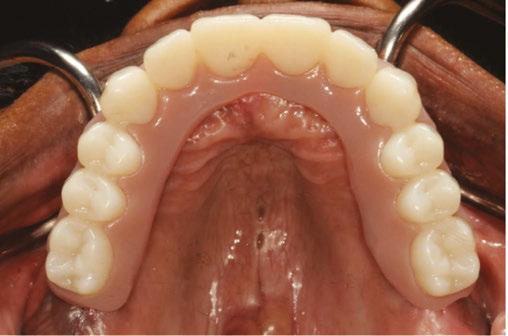

Figure 1 (left): Radiographic example of soft D4 bone. Figure 2 (right): Radiographic example of more dense D1/D2 bone

Implant design can play a significant role in the immediate-load process. Considerations include choosing an implant with appropriate width and length for the desired anatomical site (generally falls between 10 mm -15 mm in length and 3.5 mm -5.0 mm in width) and the use of a tapered implant design. Implants with deeper thread depths and shorter thread pitches can increase the bone-to-implant contact and increase primary stability5 (Figure 4 shows a visual of these terms). V-shaped threads are more aggressive and allow for greater stability of implants, while more square-shaped threads allow for greater distribution of stress and greater bone-to-implant contact.6 An implant design that is self-tapping is also advantageous for increasing primary stability.7 Although drilling protocols for osteotomies are guided by manufacturer’s recommendation, in general, primary stability can be increased when the osteotomies are under-prepared in width.8